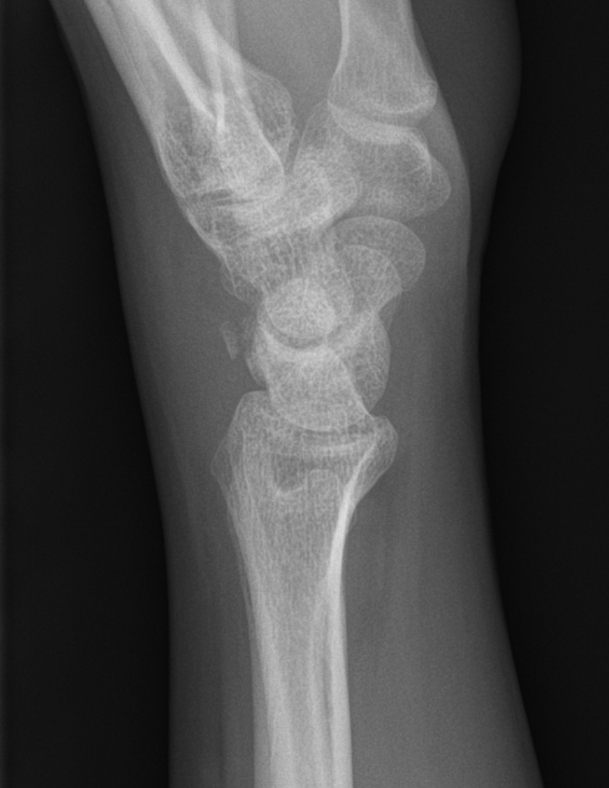

Triquetral fracture dorsal bone fragment